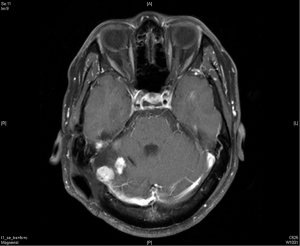

A 36-year-old man with no significant past medical history presented to the outpatient department in November 2009 with fever up to 40 degrees Celsius and headache over the posterior head region for 2 days. With the suspicion of meningitis, a brain magnetic resonance imaging (MRI) was done which showed a 57 mm × 40 mm × 70 mm lobulated extra-axial tumor over the right cerebellar tentorium with focal mass effect and resultant mild secondary non-communicating obstructive hydrocephalus (Figure 1). The possibility of extra-axial tumor such as pedunculated meningioma was considered. He underwent an excision of the lobulated mass which was sent for histopathological diagnosis. This revealed randomly oriented monomorphous tumor cells with little intervening fibrosis. The cytoplasm was scant and cell borders were indistinct. The nuclei were round to oval with moderately dense chromatin, inconspicuous nucleoli to focal areas of vesicular nuclei and mild to moderate atypia. The mitotic activity was mildly increased. No necrosis was seen in the sections. Focal mild hemorrhage and embolization material in vessels were noted. The immunohistochemical study demonstrated positive for CD34, CD99, and reticulin along with an increased Ki-67 proliferative index suggestive of a HPC.